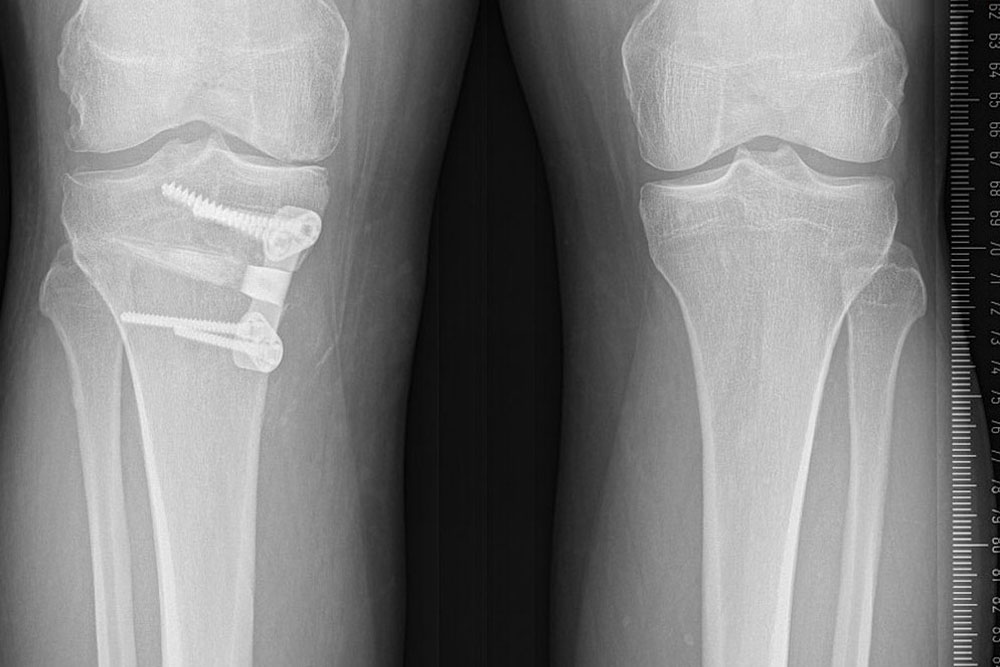

HTO High Tibial Osteotomy

A surgical procedure that realigns the knee joint.

For Young patients who have knee arthritis, this surgery can delay or prevent the need for a partial or total knee replacement by preserving damaged joint tissue.